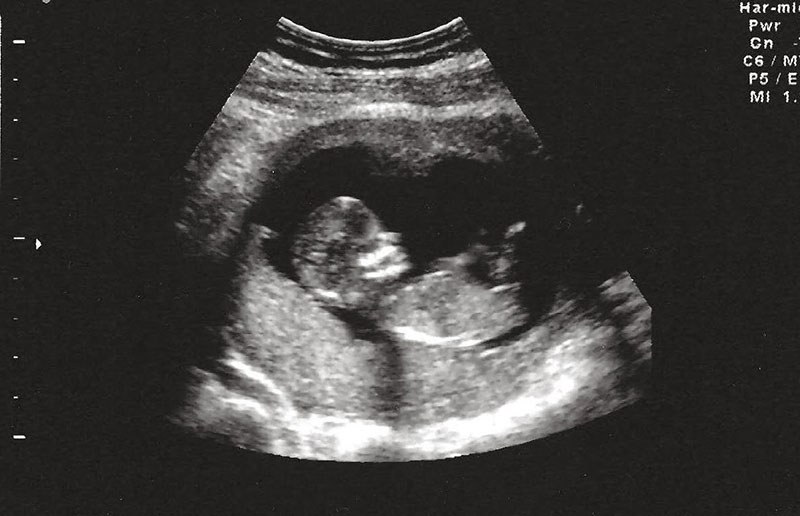

Đến lần mang thai thứ 5, em làm xét nghiệm NIPT, kết quả bình thường, em thở phào nhẹ nhõm. Em tin, có lẽ ông trời đã thương. Nhưng đến tuần thứ 20, bác sĩ nói chân tay con bị khèo… rồi mọi hy vọng lại sụp đổ thêm lần nữa.

4 năm hôn nhân, 5 lần mang thai nhưng đều mất con, người phụ nữ đau khổ nhìn chồng cũ lấy vợ mới- Ảnh 1.